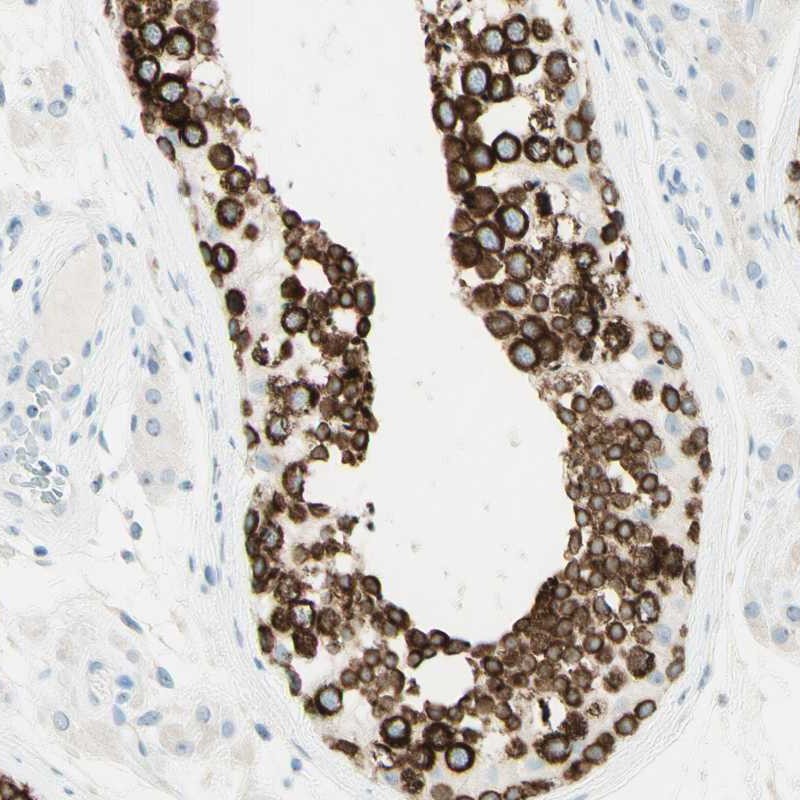

Immunohistochemistry analysis in human testis and endometrium tissues using Anti-FMR1NB antibody. Corresponding FMR1NB RNA-seq data are presented for the same tissues.